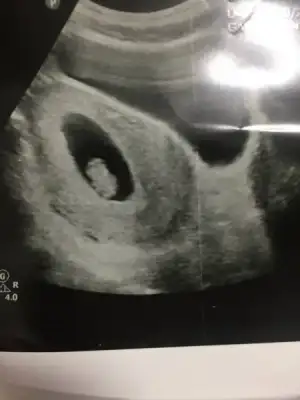

Teyzoslari bakin benim minik kurabiyem kocaman oldu bugun kontrolumuz vardi icimde kipir kipir hareket ediyordu cok duygulandim elimde olsa Sabah a kadar izlerdim onu ilk Hamilelik olunca acaip oluyorum farkli hissediyorum :emir_bebek::anneadayı:

Eklentiler

• IMG_2161.webp

IMG_2161.webp

12,6 KB · Görüntüleme: 91